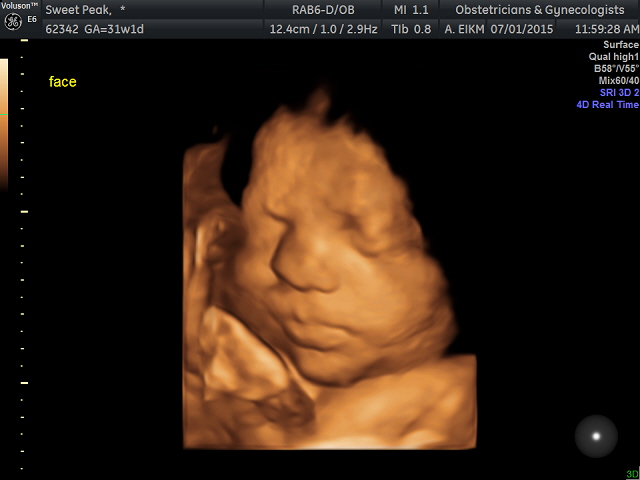

Here are some of mine. I didn't get a good view of his face during the anatomy scan, so I decided to do the elective. My little boy is 31 weeks :)

Due Sept. 1 - but hang out in both month clubs, just in case ;)